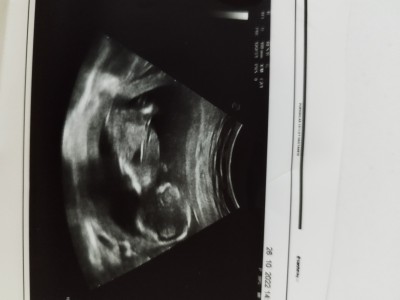

image

bu daha bugün çekildi 13 4

Erkek canım :)

(701 puan) tarafından

Hayırlısı cnm Dr bişey demedi bir tane oğlum var sağlıkla gelsin inşallah nerden anladın merak ettim :)